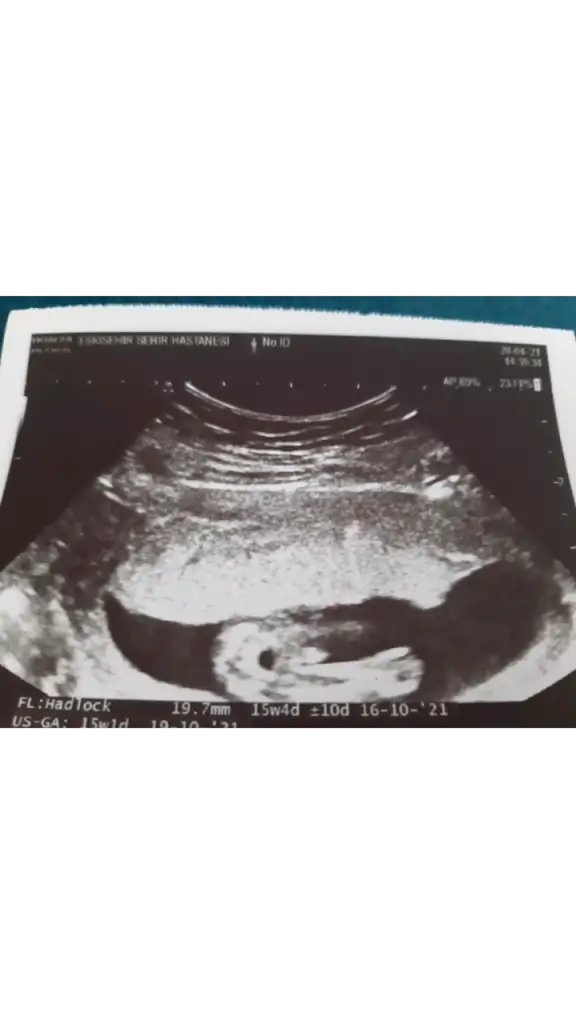

En son USG de bebek Bağdad kurmus ayakları var kapatmış diğer USG de çok net değil ama sanki gibiBunları bakarmısın cnm ikra meyra 12haftalık

Tahmininiz ne acabaEn son USG de bebek Bağdad kurmus ayakları var kapatmış diğer USG de çok net değil ama sanki gibi